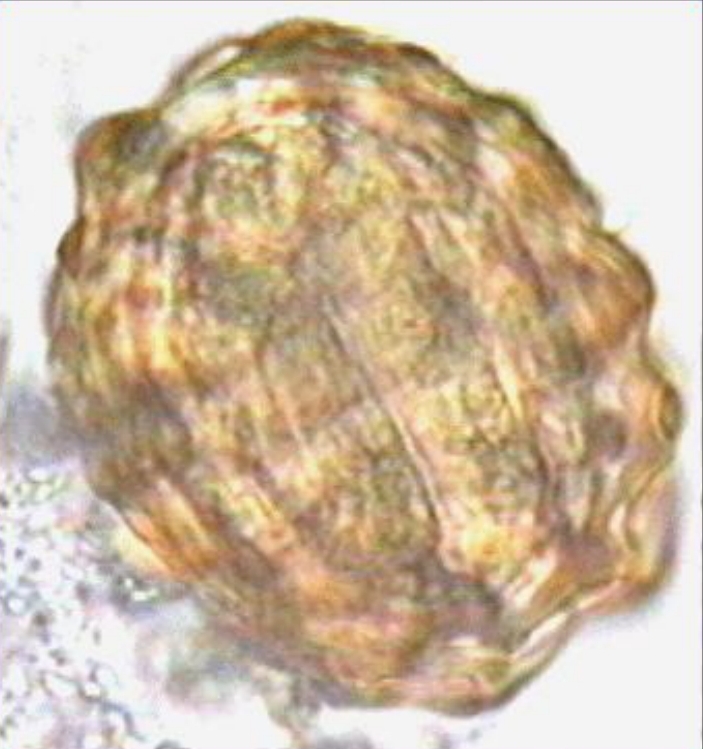

Ascaris lumbricoides fertilized corticated egg (diagnostic stage)